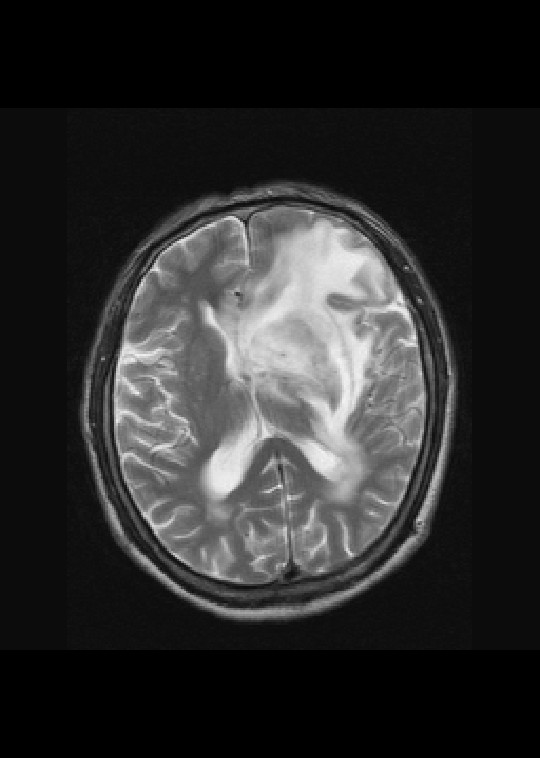

左侧基底节区异常强化信号,考虑胶质瘤。

基底节区团块样强化,淋巴瘤。

左侧基底节异常信号,水肿带明显,强化明显,考虑胶质瘤

左侧基底节区病灶t1wi呈不均匀稍低信号,t2wi呈稍高信号,周围伴有水肿。增强扫描呈均匀团块样或者抱拳样明显强化,相邻的柔脑膜亦见线样强化。首先考虑淋巴瘤。可惜没有ct平扫,如果ct平扫病灶呈高密度,那么更支持pcnsl的诊断。

左侧基底节区长t1长t2异常团块状信号,增强呈明显均一强化,水肿明显,挤压侧脑室前脚,本人考虑为胶质瘤可能性大。

首考淋巴瘤,不太支持胶质瘤。

左侧基底节区病灶t1wi呈不均匀稍低信号,t2wi呈稍高信号,周围伴有水肿。增强扫描呈均匀团块样或者抱拳样明显强化,首先考虑淋巴瘤。